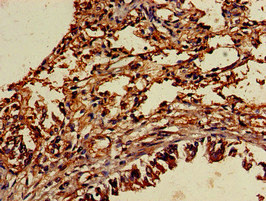

Immunohistochemistry of paraffin-embedded human lung tissue using CSB-PA025396LA01HU at dilution of 1:100